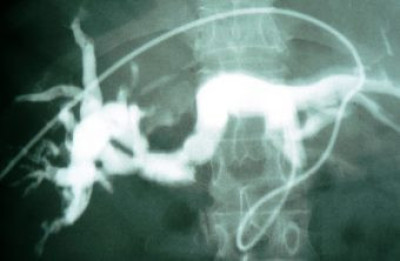

Derivación externa segmento III

Envíado por Dr. Carlos Miguel Zavaleta Consuegra